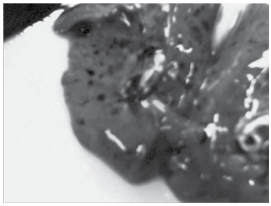

A figura a seguir mostra o bloco torácico (pulmões e cora- ção) durante a necropsia de natimorto para caracterização da causa do óbito.

Os pulmões acham-se colapsados e nota-se a presença das manchas ou petéquias de Tardieu em pleura. É correto afirmar que

Os pulmões acham-se colapsados e nota-se a presença das manchas ou petéquias de Tardieu em pleura. É correto afirmar que